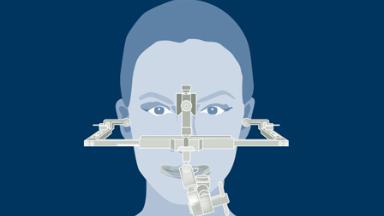

通过辅助诊断检查,可确定和评估位点特定的外科和修复要求。这有助于尽量减少种植治疗后的并发症和失败风险。

- 在制定种植治疗计划时识别辅助诊断检查的适应症

- 描述不同的辅助诊断检查